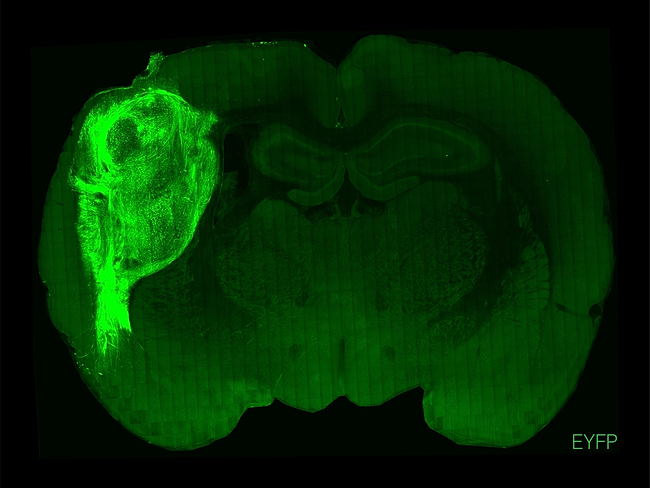

A transplanted human organoid in a section of the rat brain.

Human brain organoids transplanted into rats could be used as an in vivo model for the study of neuropsychiatric diseases. Researchers at Stanford University managed to mature human organoid neurons in the somatosensory cortex of the animal's brain and incorporate them into its neural circuitry.The integration improved the morphological and physiological properties of the transplanted neurons. Compared to those of organoids in a Petri dish, human cells preserved their own identity, and they modified the rat's learned behavior through stimulation and reward experiments.